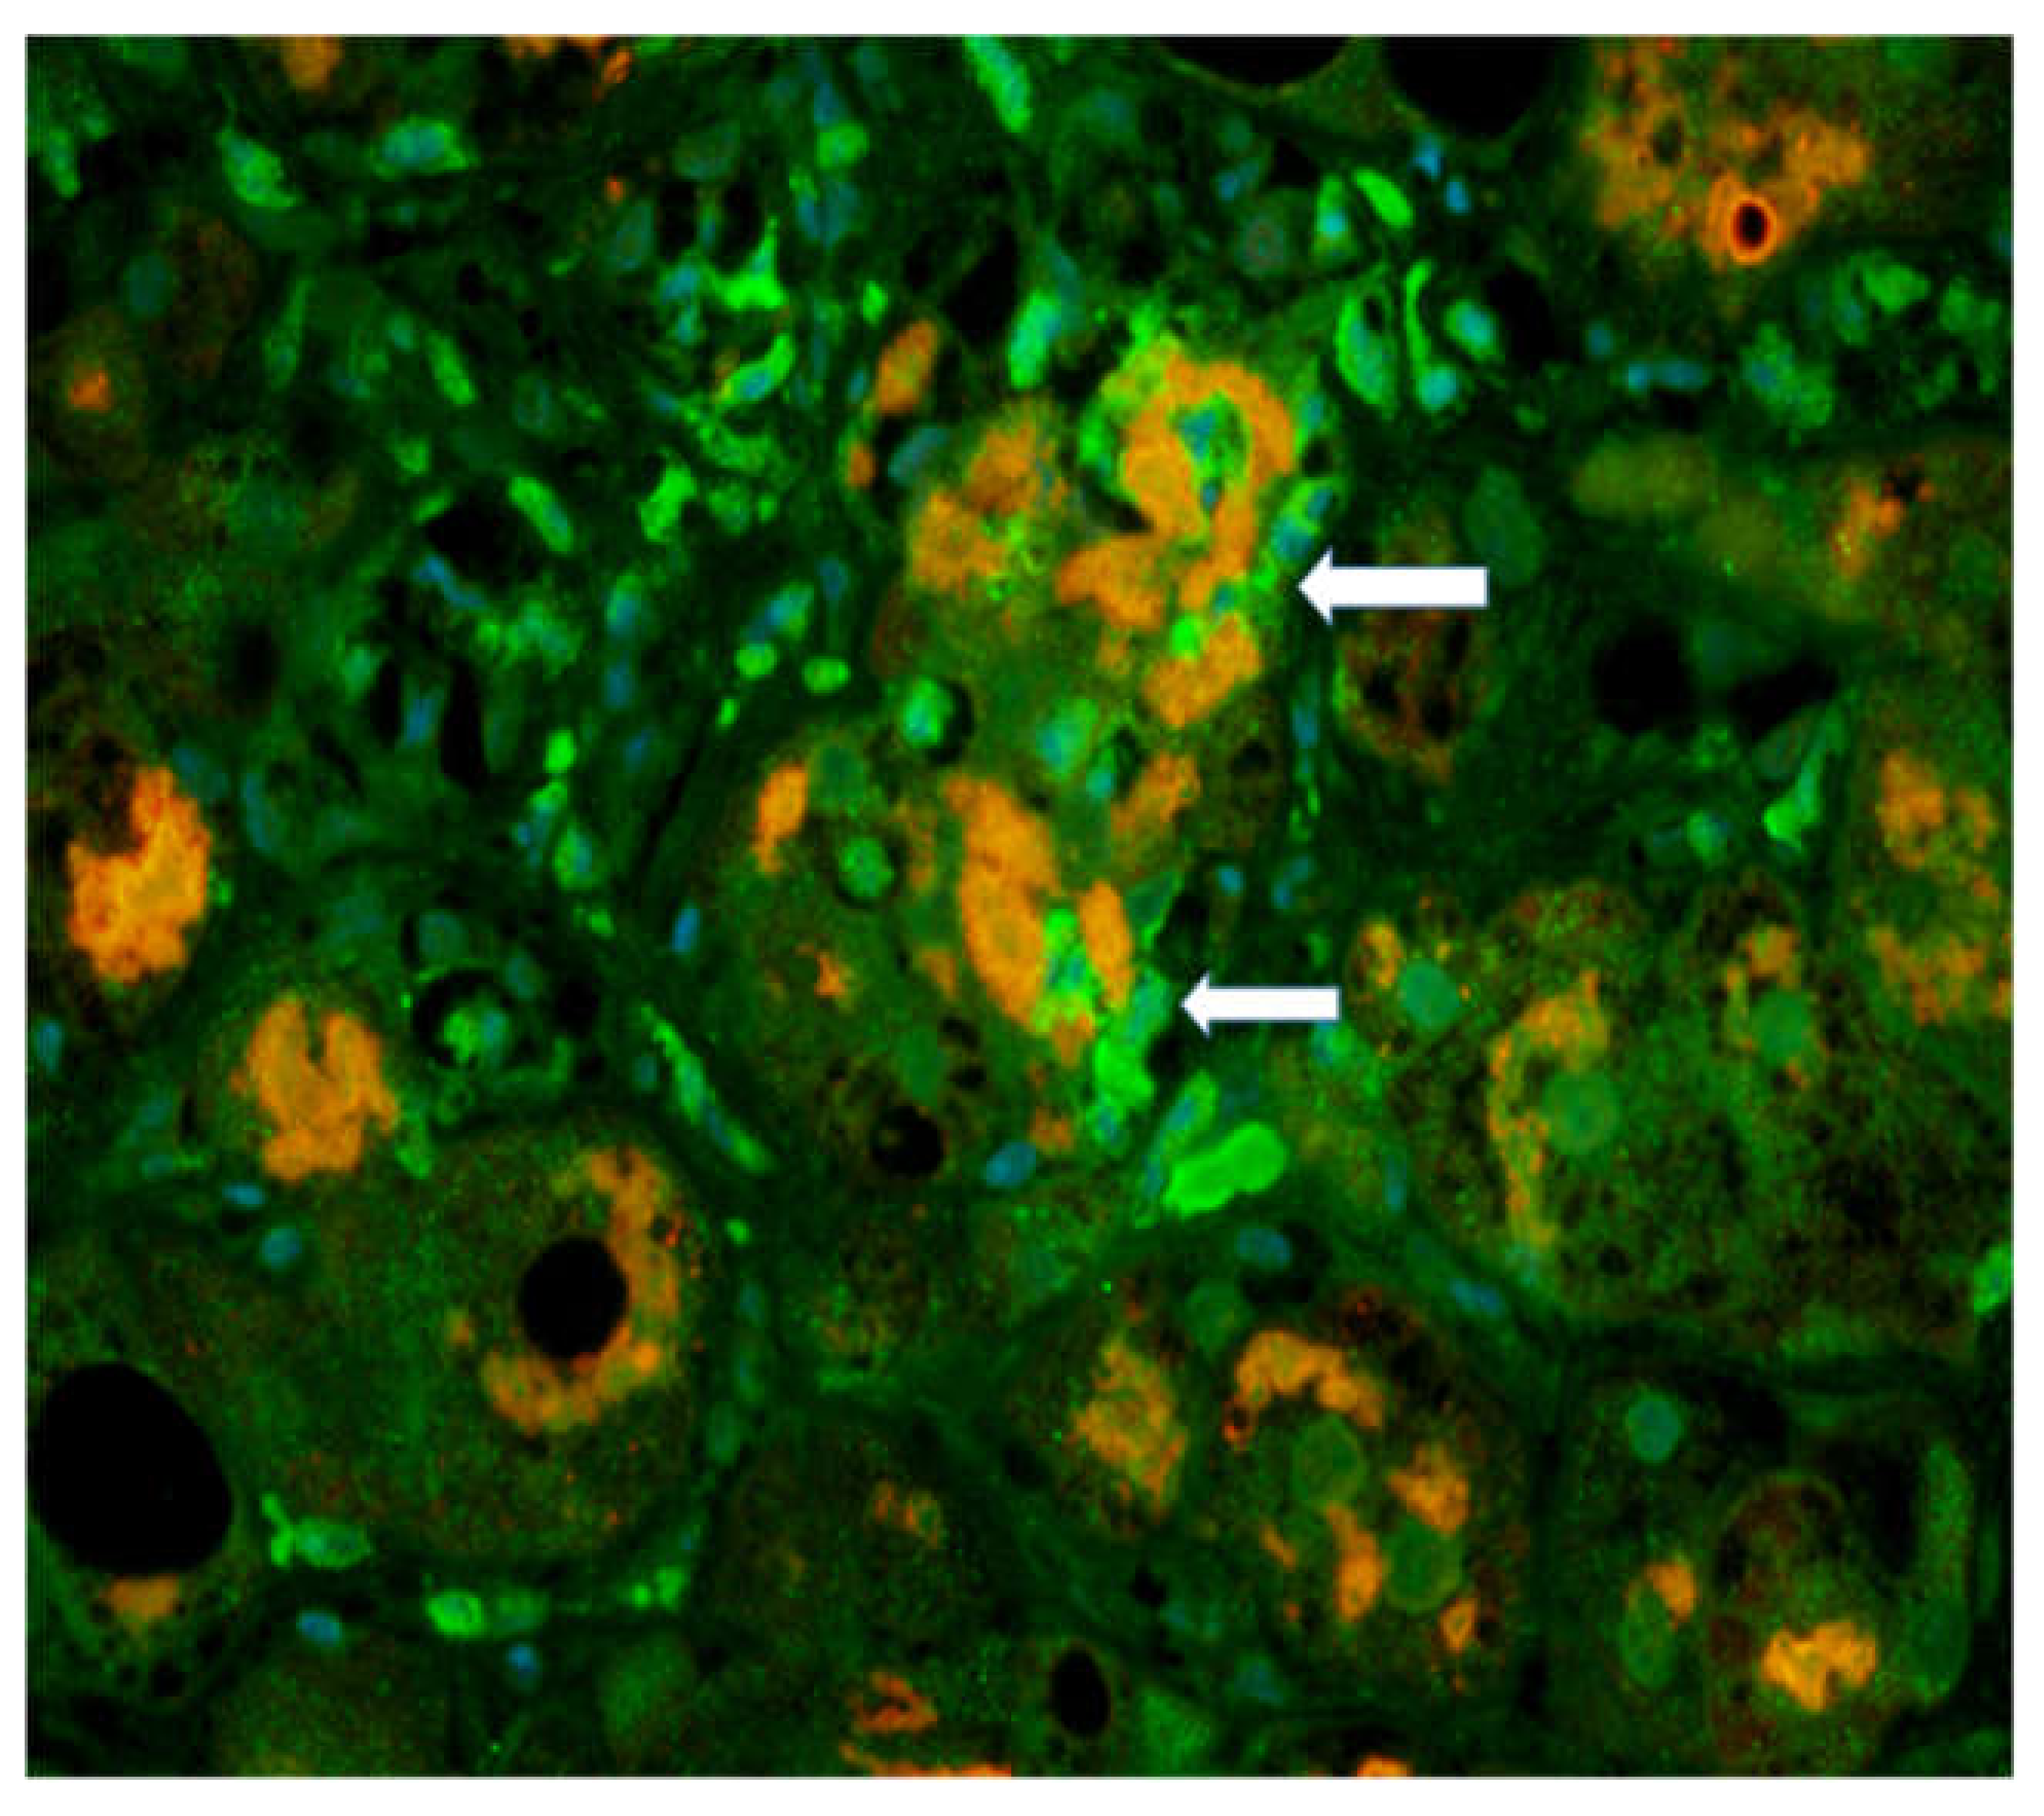

The antibody for GNA15 (canine nucleotide-binding protein Alpha 15) was used to stain the neutrophils in the liver biopsies. The antibody to ubiquitin was used to stain MDBs using a double IHC stain (Figure 1).

Immunofluorescent (IHC) staining of polymorpho-neutrophil cells (PMN)s with a GNA15 antibody showing neutrophils (arrows) (green) and Mallory Denk Bodies (orange stain) showing satellitosis × 200. Original figure is adapted from (Luo C, et al. 2018. Exp Cell Res 365: 1-11). No copywritting permission is required.

MDB forming hepatocytes were surrounded by neutrophils. The expression of GAN15 was up-regulated in AH biopsies compared to control livers.

The biopsy slide was stained with an antibody to myeloperoxidase as well as Hematoxylin & Eosin (H&E) staining [39] showing numerous neutrophyils, similar to those seen in Figure 1. This confirms that the GNA15 stained positive for neutrophyils. The myeloperoxidase stain also showed that sinusoids were filled with numerous neutrophyils. Electron microscopy of the liver biopsies showed satellitosis of the granulocytes around and next to the MDB-forming hepatocytes (Figure 2).